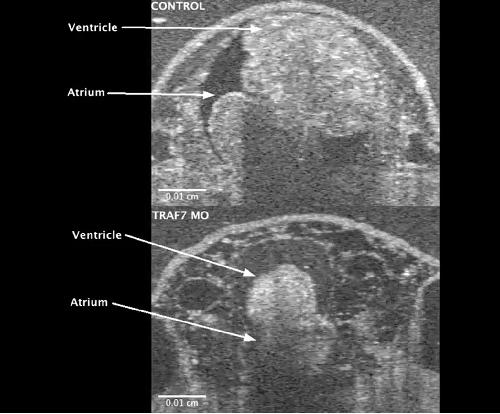

Pleiotropic role of TRAF7 in skull-base meningiomas and congenital heart disease., Mishra-Gorur K, Barak T, Kaulen LD, Henegariu O, Jin SC, Aguilera SM, Yalbir E, Goles G, Nishimura S, Miyagishima D, Djenoune L, Altinok S, Rai DK, Viviano S, Prendergast A, Zerillo C, Ozcan K, Baran B, Sencar L, Goc N, Yarman Y, Ercan-Sencicek AG, Bilguvar K, Lifton RP, Moliterno J, Louvi A, Yuan S, Deniz E, Brueckner M, Gunel M., Proc Natl Acad Sci U S A. April 18, 2023; 120 (16): e2214997120. |